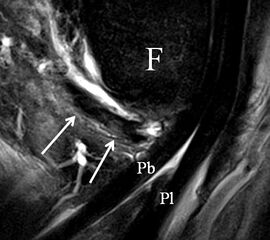

Der Ursprung des Ligamentum fibulocalcaneare liegt unmittelbar kaudal und dorsal des Ursprungs des Ligamentum fibulotalare anterius, so dass gehäuft kombinierte Verletzungen und auch ein gemeinsamer knöcherner Ausriss beobachtet werden. Nach kaudal dorsal verläuft das Band dann nach medial konvex unter die Peroneussehnen. Danach ist ein schräg deszendierender, gestreckter Verlauf bis zum calcanearen Ansatz abgrenzbar (Abb. 10). Dieser zu allen drei Standardebenen schräge Verlauf erschwert häufig die Diagnostik des LFC vor allem bei subtileren Verletzungen. Spezialprojektionen, die dem Bandverlauf orthograd folgen (entweder schräg coronar oder schräg sagittal) erleichtern auch hier die Diagnostik (Abb. 11) insbesondere nicht dislozierter Avulsionen. Assoziierte Verletzungen der Peroneussehnenloge müssen mit beurteilt werden, wobei neben Verletzungen der Sehnen und Sehnenscheiden die Beurteilung des Retinaculum peroneum superius und inferius wichtig ist. In einem Kollektiv von Patienten mit chronischen Außenbandinstabilitäten weisen 50% der Patienten eine Verletzung dieser Strukturen auf 5. Auch hier erleichtern hochauflösende Techniken die Diagnostik (Abb. 12).